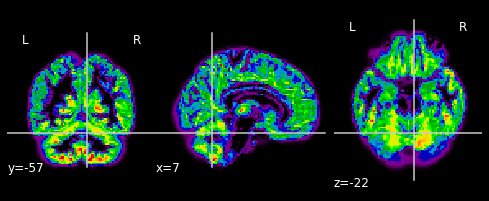

… and plot their gray matter densities.

for i in range(n_subjects):

plotting.plot_epi(gm_imgs[i])

plt.show()